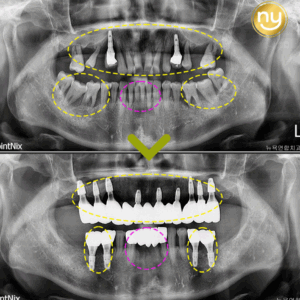

위 환자분은 충치가 많이 진행되어 신경치료한 치아를 사용하고 있었습니다.

하지만, 오랜 기간이 지나 치아 뿌리 끝에 염증이 생겨 발치를 권유받았는데요,

따라서 CT 촬영을 통한 정밀한 진단 및 분석으로

뿌리 끝 염증을 세심히, 섬세히 관찰할 수 있어야 합니다.

위 환자분은 재식술에 성공해 신경치료 후,

염증을 해결하고 내 치아를 살려 사용할 수 있게 되었습니다.